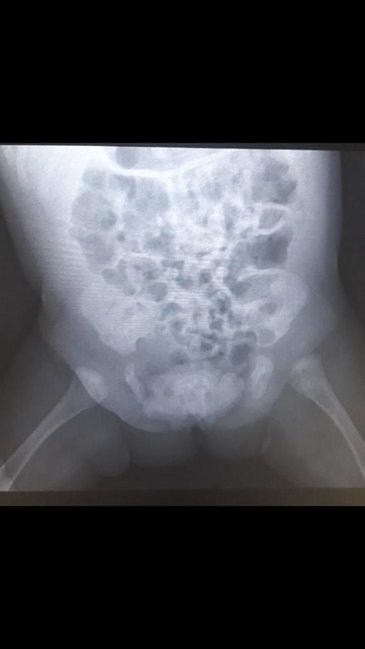

"Uşağa sidik kisəsi ekstrofiyası diaqnozu qoyularaq cərrahi əməliyyat planlaşdırıldı. Əməliyyatdan öncə çəkilən rentgendə qasıq sümükləri arasındakı məsafə böyük olduğu üçün uzman travmatoloq Fərhad Verdiyev qasıq sümüklərini yaxınlaşadıra bilmək üçün arxadan qalça sümüklərini kəsdi.

Sidik kisəsi ekstrofiyasının təmiri əməliyyatını uğurla icra etdik", - deyə cərrah qeyd edib.